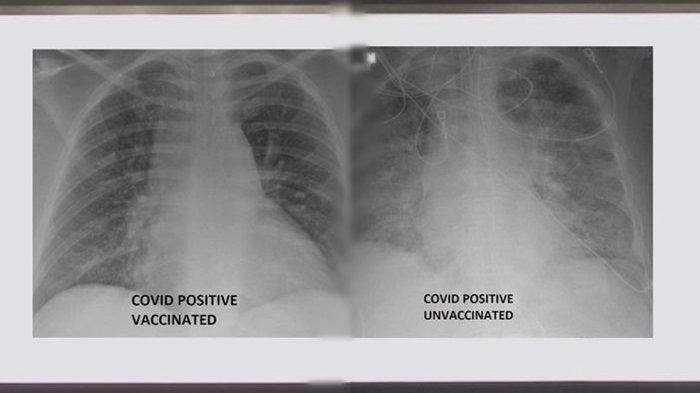

Paru-paru pasien Covid yang belum divaksinasi terlihat dipenuhi virus, sementara paru-paru pasien yang sudah divaksin terlihat lebih bersih

Hasil rontgen paru-paru pasien Covid-19 yang tidak divaksinasi ternyata berbeda dengan yang sudah divaksinasi.

Paru-paru pasien Covid yang belum divaksinasi terlihat dipenuhi virus, sementara paru-paru pasien yang sudah divaksin terlihat lebih bersih, sebagaimana kondisi normal.

Dilansir dari The Independent, Rabu (4/8/2021), ada dua gambar sinar-X yang disediakan oleh SSM Health.

Keduanya dari pasien yang terinfeksi, tetapi satu dari orang yang divaksinasi dan satu dari orang yang belum diinokulasi.

Kedua foto pemindaian itu menunjukkan perbedaan dampak virus di paru-paru antara orang-orang dengan status vaksinasi yang berbeda.

Untuk melindungi informasi pasien, kondisi spesifik yang terlihat pada sinar-X tidak diungkapkan.